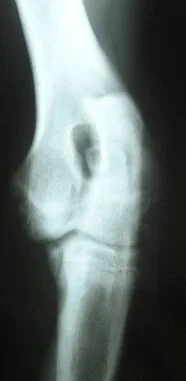

En la mayoría de los casos, las radiografías pueden confirmar los hallazgos y caracterizar el tipo y la severidad de la displasia de codo. A pesar de ello, en determinadas ocasiones es necesario recurrir a métodos de diagnóstico más avanzados como la artroscopia, TAC o resonancia magnética.

La fragmentación del proceso coronoides medial es la forma más común de presentación de displasia de codo en perros. En este caso, los huesos y cartílago de la parte más interna (medial) del codo, sufre una fragmentación de leve a severa que deriva en una osteoartrosis. Los fragmentos que se forman pueden permanecer en su lugar o moverse en la articulación como una piedra en un zapato. La artroscopia realizada por un cirujano experimentado permite un diagnóstico seguro al mismo tiempo que un tratamiento inmediato. De forma mínimamente invasiva el cirujano puede explorar la articulación, eliminar el fragmento y tratar el cartílago de alrededor. Este procedimiento suele durar de media entre 20 a 45 minutos por articulación. La artroscopia tiene un alto éxito para la extracción del cartílago y los huesos alterados reduciendo la evolución a la artrosis y mejora la situación clínica. El paciente se recupera rápidamente en el postoperatorio al ser una técnica de mínima invasión comparada con la cirugía convencional. Pero la artroscopia no es la cura de la osteoartrosis, seguirá evolucionando y debe ser controlado a lo largo de su vida y probablemente requiera otros tratamientos a lo largo de ésta.

Con la edad, la osteoartrosis debida a la fragmentación del proceso coronoides medial y las otras formas de displasia de codo, dará lugar a la pérdida del cartílago en las superficies articulares de apoyo, lo que se llama “Enfermedad del compartimento medial”. Esto es el estadio final donde se produce un colapso articular y el roce del hueso sobre hueso sin que el cartílago que lo protege. En cambio, el cartílago de la parte lateral de la articulación suele permanecer en buen estado en la mayoría de los casos.